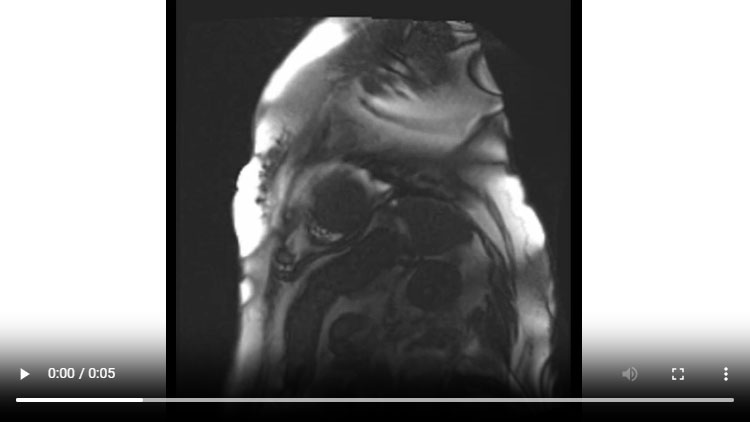

Figure 1B : Séquence Ciné-IRM - Coupes petit-axe médian

- Présence d’une hypertrophie ventriculaire gauche (HVG) asymétrique à prédominance septale mesurée au maximum à 23 mm.

- Visualisation de la sonde de PM avec artéfacts métalliques modérés au niveau du ventricule droit (flèches roses).

- Présence d’un épanchement péricardique de moyenne abondance (flèches rouges).